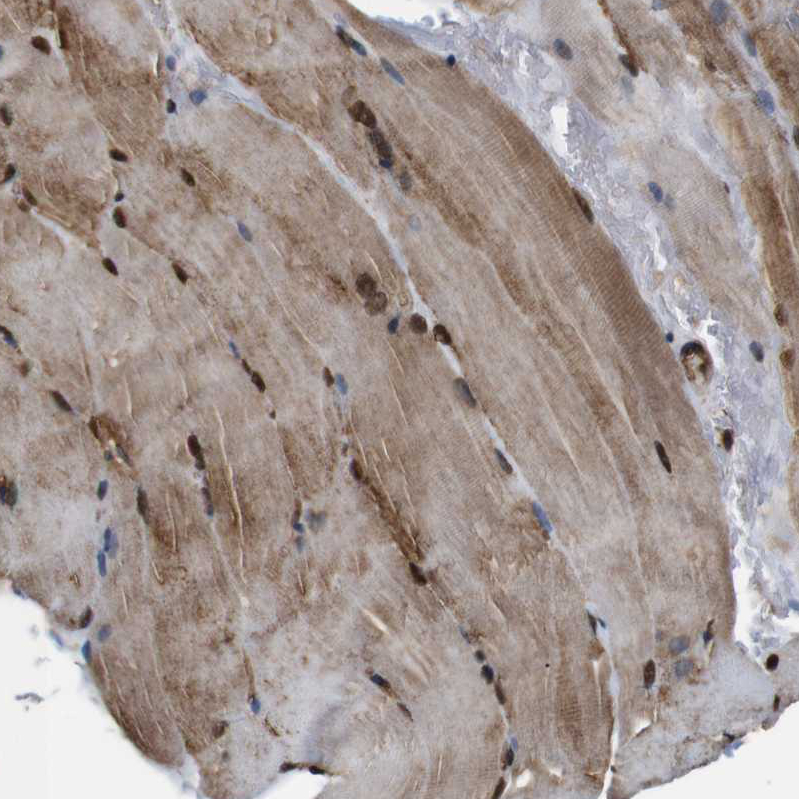

Immunohistochemical staining of human prostate shows strong nuclear and cytoplasmic positivity in glandular cells.